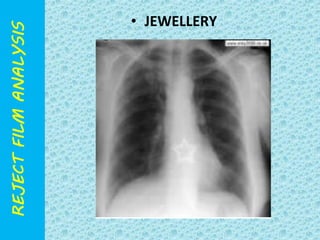

• JEWELLERY